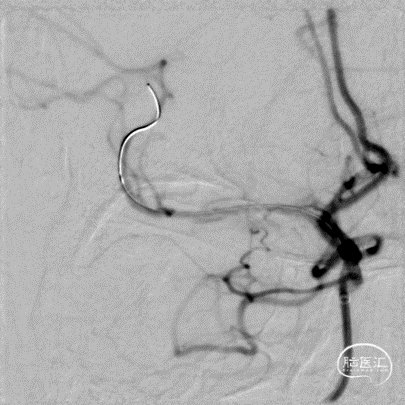

释放支架后造影见支架中段稍有残留狭窄,以8atm缓慢再扩张,残留狭窄消失。

最后工作位造影和正侧位造影,右侧大脑中动脉区域血流恢复,灌注满意。

术后CT无出血,术后患者未诉不适,无新发神经功能症状及体征,继续予以抗栓、强化降脂、调节血糖等治疗。